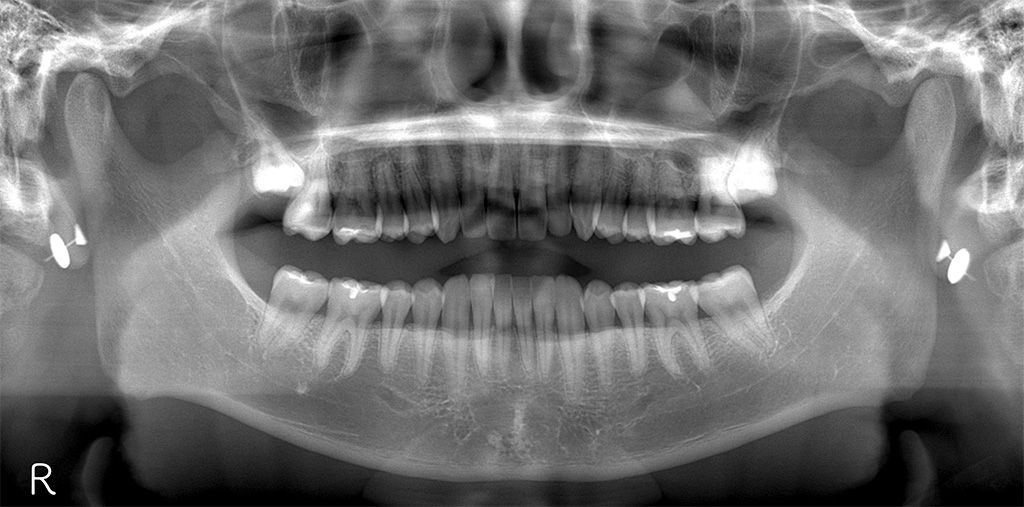

● 初回(フロス経験ゼロ)

カリエスがなく歯科医院に縁がない患者さんの、よくある口腔状態でスタートしました。